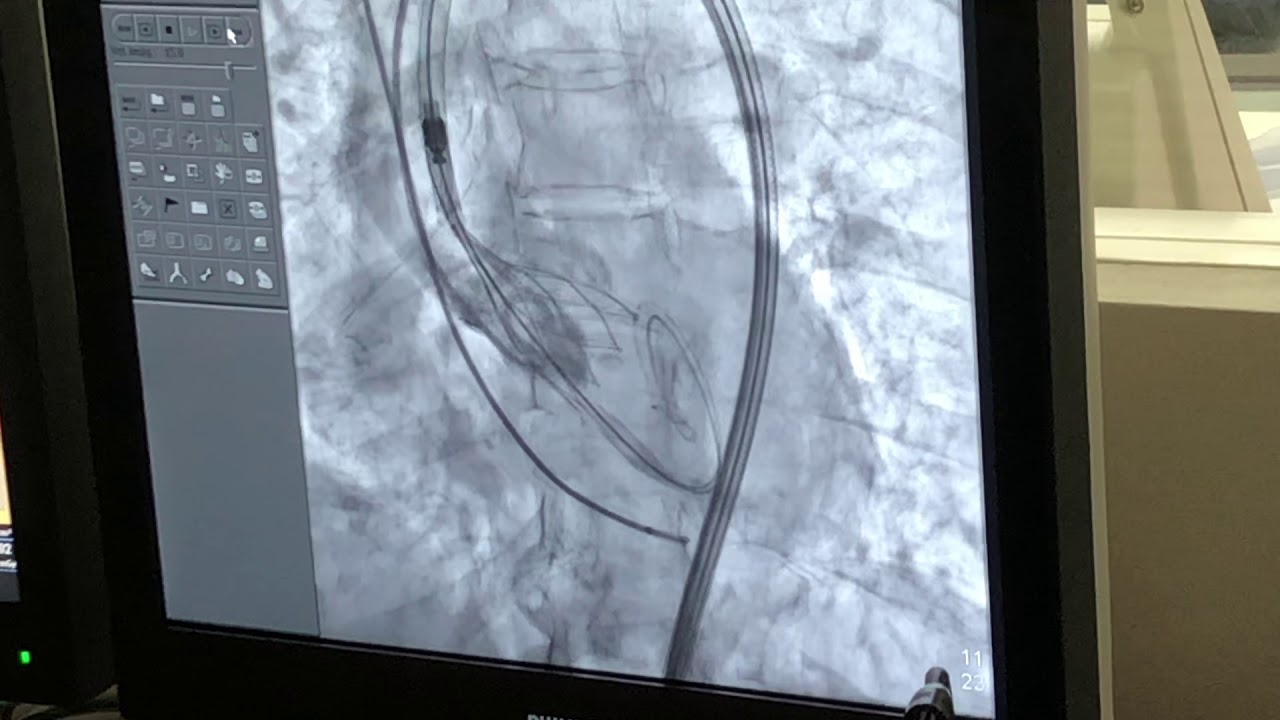

Realicé mi formación como médico general en la Universidad Autónoma de Veracruz Villa Rica, posteriormente la especialidad en medicina interna durante dos años en centro medico nacional Adolfo Ruiz Cortinez UMAE 14 en Veracruz, recibiendo en el primer año el reconocimiento por excelencia académica y en el segundo año reconocimiento al mejor promedio de mi generación. Realicé la subespecialidad en Cardiología clínica en el Centro Médico Nacional “La Raza”, en la Ciudad de México siendo jefe de residentes en el último año de la residencia médica, durante el tiempo la sede recibió el premio a la mejor cede de formadores de cardiología 2012-2013 premio otorgado por Dr. Enrique Graube (en ese entonces Director de medicina UNAM). Entre mis actividades asistenciales y conferencias, he presentado trabajos libres a nivel internacional (congreso de falla cardiaca lisboa 2013, Congreso mundial de cardiologia 2016, 2018 en AHA) ganador del premio internacional “la imagen más bella en cardiología, sociedad europea cardiologia España 2013”, así mismo presentación de más de 35 articulos publicados en revistas indexadas, soy miembro de la sociedad mexicana de cardiología no. 2076, asociación mexicana de cardiología, Fellow in training de la American collegue of cardiology capítulo México. Miembro de la sociedad europea de cardiología ESC ID 509395. Médico adscrito en el centro médico nacional la Raza, fui profesor adjunto del curso de cardiología en el mismo centro y sindal en el exámen de certificación de cardiología clínica de la sociedad mexicana de cardiología. Desde el 2016-2018 realicé curso de alta especialidad en electrofisiología cardiaca y estimulación cardiaca , realizando cursos fuera del país para especialización en técnicas avanzadas de ablación de arritmias, actualmente me encuentro realizando en el segundo año de la maestría en Dirección y Gestión de Instituciones de salud y Especialidad en Gestión de la Salud y Bienestar Corporativo